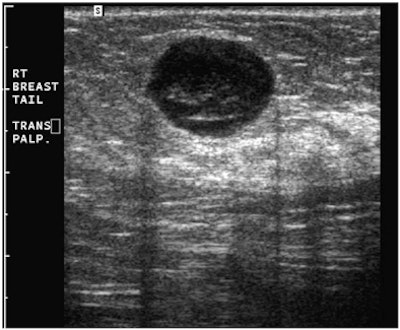

"A simple, yet powerful application of PDUS is differentiating between a rounded, markedly hypoechoic tumor and a [thickened] cyst with low-level internal echoes," he said. "The detection of the smallest vessel within the lesion automatically excludes a cyst -- or any other fluid collection -- and confirms a neoplasm. This very simple yet very useful application of PDUS is still underused."

| Images are of a circumscribed round pseudocystic mass. Above, grayscale US shows a cystic appearing mass with some low-level internal echoes. Below, PDUS performed with only minimal pressure applied through the probe shows internal vascularity, thereby excluding a fluid-filled lesion and confirming a tissular mass. Fine-needle aspiration readily confirmed a metastasis from a uterine leiomyosarcoma treated six years previously. All images courtesy of Dr. Bruno Fornage. |